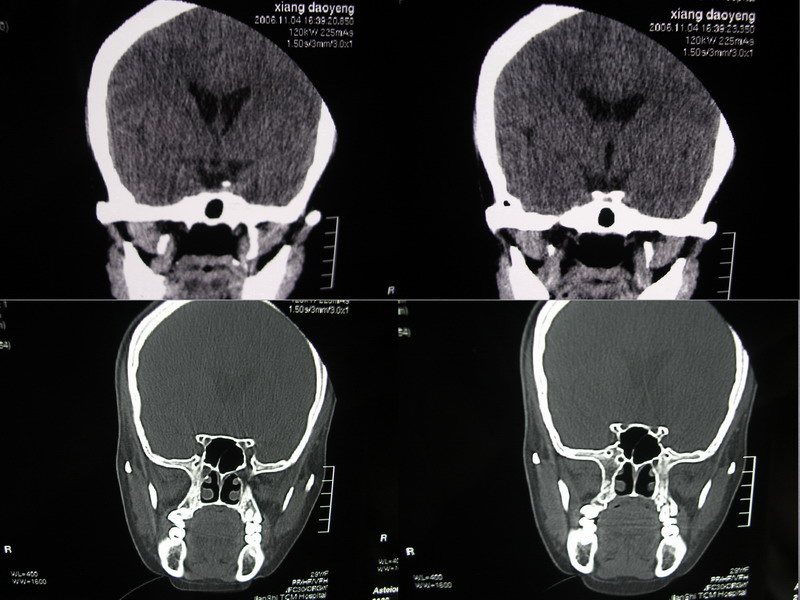

向××,女,29岁,二十天前高热,抗炎治疗后双眼斜视,肌无力,双下肢张力ii级。

奇怪啊!临床症状那么典型,为什么没有什么脑炎的迹象?二十天了,应该有表现的,是我眼拙?但小脑蚓部以及左侧颅中窝均属正常我应该没有看错,大汗淋漓!渴望老师们指点迷津!

除侧脑室额角轻度扩大外,余未见异常。

感觉胼胝体有异常,但看不出异常影像特征,建议行mri进一步确诊.

侧脑室稍扩大,余未见确切异常强化征,请结合脑脊液及脑脊髓mri检查

侧脑室稍扩大,余未见明显异常强化征。

双侧脑室有轻度扩大,增强看脑沟裂显示还是模糊的.时间较长应该考虑脑膜炎.